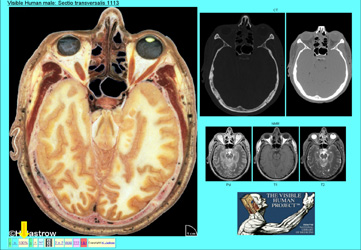

Eines dieser Produkte ist der Homo sapiens dissecatus. Dieser Atlas beinhaltet das gesamte Bildmaterial des Mannes (Abb.4). Der zugehörige Originaldatensatz umfasst in komprimierter Form ca. 39 GB. Das sind 55 randvolle CDs. Hier sehen Sie technische Details dazu. Weitere finden Sie auf Ihrem Informationsblatt. Das faszinierende ist, dass alle Daten vom selben Individuum stammen, daher entsprechen z.B. die unten gezeigten radiologischen Bilder dem oben demonstrierten Schnitt durch das Gehirn.

Es wird die in Abb.21 gezeigte Übersichtsseite geladen. Die Drüse ist auf den hervorgehobenen Schnitten zu erkennen. Wenn wir auf das markierte Miniaturbild klicken, erscheint die Seite mit dem digitalisierten Schnitt und den zugehörigen CT und NMR Aufnahmen (Abb.22). Um mehr erkennen zu können, klicken wir den 100% Knopf an. Abb.22

In Abb.27 sehen Sie eine Seite des Brustraums mit den zugehörigen CT und NMR Abbildungen. Man erkennt die beiden Herzkammern, den rechten Vorhof und die Lungen, die Wirbelsäule, Rippen und Muskeln der Oberarme.